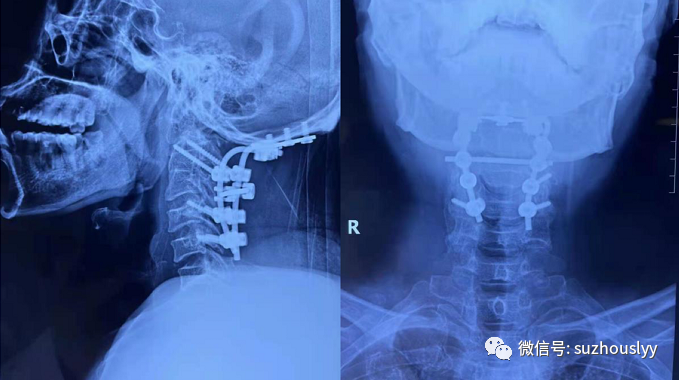

近日,我院脊柱外科团队在麻醉科手术室团队、ICU团队共同协作下成功开展一例颈椎后路枕颈融合+C0-C5椎管减压+枕颈顶棒系统内固定术。该手术的成功开展不仅解决困扰患者的病痛,也标志着我院脊柱外科的医疗水平迈上了一个新台阶。

患者,男,47岁,因颈背部疼痛伴双上肢麻木、下肢无力、跛行入院。就诊当地医院行辅助检查可见MR见颈2/3、3/4椎间盘层面椎管狭窄,延髓内脊髓变性。颈椎CT见寰椎与枕骨局部融合,寰椎后弓未融合,颈2及颈3椎体、椎板及棘突融合。当地医院建议手术治疗,因该手术难度及风险极大,建议外院治疗。患者辗转数家医院后,就诊我院脊柱外科,经专家诊断为:颅底陷凹症、寰椎后弓二分裂、先天性颈3、4融椎并发育性寰椎管狭窄症。枕骨大孔狭窄及发育性寰椎管狭窄压迫到延髓可以有呼吸窘迫等严重症状,并可出现类似于下颈椎的脊髓病变:感觉和运动功能障碍,行走障碍,括约肌功能障碍和共济失调等。一旦出现脊髓神经受压症状,应考虑手术治疗。脊髓减压可以根据受压部位选择前路或后路手术,固定多考虑采用寰枕融合术或椎弓根钉固定并融合。通过C0-C5椎管减压解除压迫、避免进一步脊髓损伤,进行后路脊柱固定和融合保持脊柱稳定性。

我院脊柱外科主任医师张栋博士,副主任医师凌嵘、时强,主治医师于振及脊柱外科团队认真开展病例讨论、制定治疗计划、评估手术风险等,并制定相关治疗细则及应急预案。与家属沟通后,决定尽快进行手术。手术历时5小时顺利完成,患者术后转入重症监护室进一步支持治疗,次日各项生命体征平稳,转入普通病房继续康复治疗。